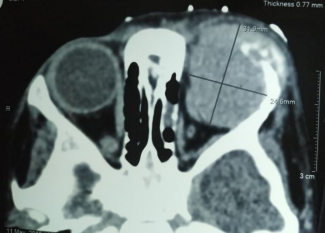

A one and half year-old boy visited Pediatric OPD with the complaints of low-grade fever, anorexia, abdominal distension, and weight loss for 15 days. His mother also complained of progressively increasing swelling of left eye for 5 days. On physical examination, patient was afebrile and moderate pallor was present. Per abdomen examination revealed non-tender, soft lump in right hypochondrium to right lumber quadrant up to midline. His weight was 7.2 kg (expected weight=12.2 kg) and height was 70 cm (expected height=87.8 cm). Ophthalmological examination revealed inferior globe dystopia and proptosis of left eye (Figure 1 and 2). Anterior segment was normal in both eyes. Fundus evaluation demonstrated choroidal folds in left eye, rest of the findings were normal in both eyes. UBM scan of left orbit showed large homogenous lesion superior to globe with mild to moderated spikes (Figure 3). The laboratory investigation revealed hemoglobin level 8g/dL, total leucocyte count 8,200/mm3, platelet count 32,500/mm3 and erythrocyte sedimentation rate 33.2mm in first hour. Twenty-four hour urinary vanilly-mandelic acid level was found to be elevated (68 µmol/mL; normal=0-10 µmol/mL). Bone marrow aspiration discovered infiltration with round cell indicative of neuroblastoma. Abdominal USG disclosed a large heterogeneously hypoechoic mass (78×30×24 cm in size) with multiple foci of calcification in right hypochondrium crossing midline causing mass effect and medially displacing aorta and inferior vena cava. Abdominal USG findings further supported by magnetic resonance imaging (MRI) which also revealed hepatic metastases. Contrast enhanced CT orbit findings reported a relatively well defined heterogeneously enhancing soft tissue mass lesion of size 32×25×27 mm in extraconal space of left orbit, possibly arising superolateral wall (frontal bone) of left orbit showing speculated/ ‘sun-ray’ periosteal reaction(Figure 4). Mass effect was evidenced by inferior and lateral displacement of left extra-ocular muscles, optic nerve, and eye globe with proptosis. USG guided true-cut biopsy of abdominal mass reveled neuroblastoma. Based on above-mentioned signs and investigations, child was diagnosed as a stage IVwith hepatic metastases and osseous metastatic lesion of left orbit. Department of Pediatric Oncology started chemotherapy (cisplatin, doxorubicin, etoposide, and ifosfamide) with injection ondansetron and injection ranitidine. On further following the child, he developed exposure keratopathy in affected eye(Figure 5). Unfortunately, child died while undergoing chemotherapy.

Figure 4. An axial contrast enhanced CT orbit reveal left eye proptosis and heterogeneously enhancing soft tissue mass lesion of size 32×25×27 mm in extraconal space of left orbit, possibly arising superolateral wall (frontal bone) of left orbit showing speculated/ ‘sun-ray’ periosteal reaction (arrow head). CT=computed tomography.